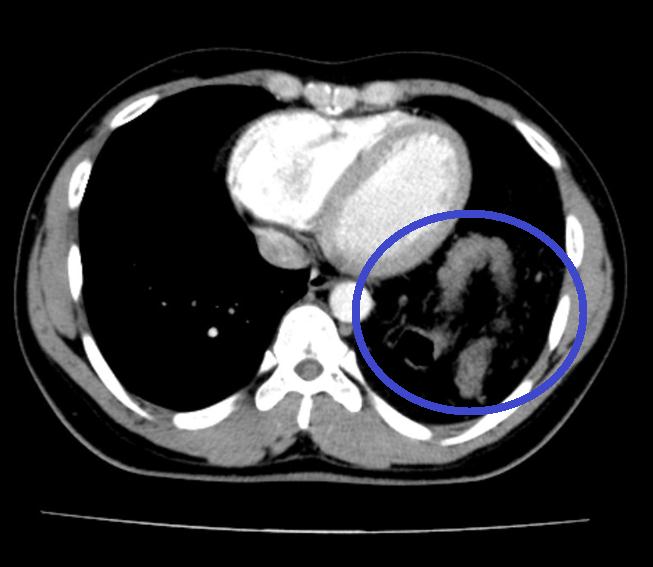

Bệnh nhân Đ.A.H, nam 25 tuổi với tiền sử khỏe mạnh. Hơn một năm trước, bệnh nhân bị tai nạn giao thông xe máy tự ngã, bị đập ngực trái xuống đường. Sau tai nạn, H. thấy đau tức ngực nhẹ, không khó thở nên không đi khám. Trong thời gian tiếp theo, H. thấy cơ thể bình thường khi sinh hoạt lao động nhẹ, chỉ xuất hiện khó thở khi khuân vác các vật nặng. Điều này chưa khiến H. cảm thấy bất thường trong cơ thể mà chỉ nghĩ đơn giản là do làm việc quá sức. Khoảng 5 tháng trước, H. bị mắc Covid-19 tự điều trị tại nhà. Tuy nhiên, sau khi khỏi bệnh, các triệu chứng ho và đau tức ngực vẫn tồn tại và có dấu hiệu nặng lên. Nghĩ mình bị hậu Covid nên H. vẫn tự điều trị tại nhà. Tuy nhiên, mộttháng trở lại đây, H. thấy đau tức ngực kèm ho và khó thở tăng lên. Đoán rằng mình đang có vấn đề về đường hô hấp sau khi mắc Covid-19 nên H. đã đi khám chuyên khoa hô hấp tại Bệnh viện Bạch Mai. Tại đây, H. đã được chỉ định chụp X.quang ngực và được phát hiện có tình trạng có hình bóng hơi của ruột ở trên ngực trái (Ảnh 1). Bệnh nhân được hoàn thiện thêm các xét nghiệm cận lâm sàng và hội chẩn thêm các chuyên khoa, chụp cắt lớp khẳng định có thoát vị tạng bụng qua cơ hoành lên ngực trái. Sau đó, H. được chuyển tới Khoa Phẫu thuật Tiêu hóa – Gan mật tụy để tiến hành phẫu thuật.

Ảnh 2: Đại tràng nằm trong ngực trái trên Cắt lớp vi tính ngực

– Cắt lớp vi tính và cộng hưởng từ: Thấy vị trí gián đoạn của cơ hoành, hình ảnh các tạng thoát vị, giúp đánh giá được thể bệnh và đưa ra phương án điều trị phù hợp.